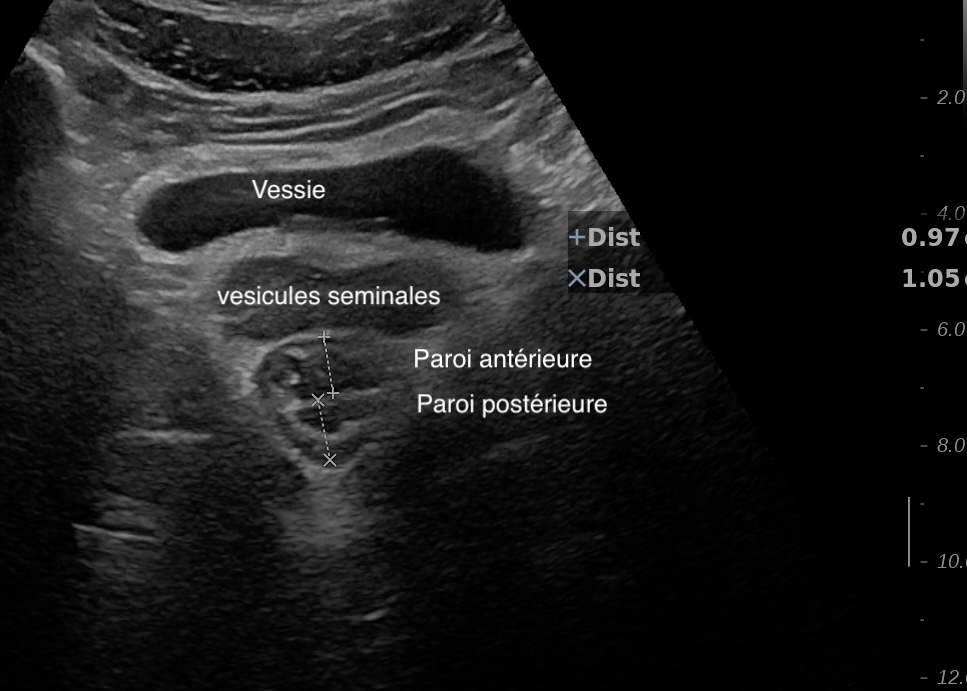

Là encore la paroi est très hypoéchogène, la structure en couches est par endroit totalement absente, ulcérations en surface, infiltration de la graisse, doppler intense, petites adénopathies périphériques.

Le rectum est bien vu avec la sonde basse fréquence la paroi atteint 10 mm à ce niveau.

Le score de Milan MUC est de (10 x1,4+2) = 16